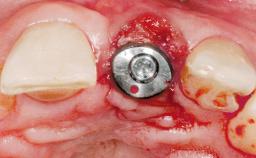

Immediate Flapless Placement of an Implant in a Maxillary Left Central Incisor Site

A 29-year-old female patient presented for treatment to replace the upper left central incisor tooth with an implant- supported restoration. The tooth had been intermittently symptomatic for the previous 12 months. The tooth had originally suffered trauma about 15 years previously. Several endodontic treatments had been performed, including an apicectomy procedure to retain the tooth. The patient was healthy and a non-smoker. She had reasonable expectations in regard to esthetic outcomes and the risk of marginal tissue recession following treatment. At medium smile, the gingival margins of the upper teeth were visible, with a display of 3 to 4 mm of the gingival margins. Gingival recession of tooth 21 and a discrepancy in the gingival levels between teeth 11 and 21 was observable during normal speech and smile.

Type of Implants One-Piece

Placement Protocol Immediate implant placement

Esthetic Risk Medium

Complexity Moderate